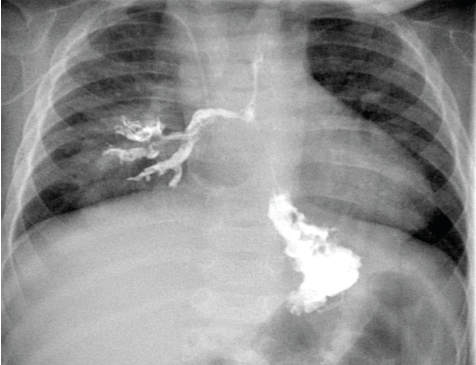

Norman M. Jacobs, MD; John H. Stroger, Jr.; Hitesh Agrawal, MD; Gunjan Dokania, MD; Aashima Bansal, MD

An 18-year-old boy presented to the emergency department (ED) with sudden-onset nausea, retrosternal chest pain, and vomiting that had been occurring more than 10 times a day for the last 4 days.